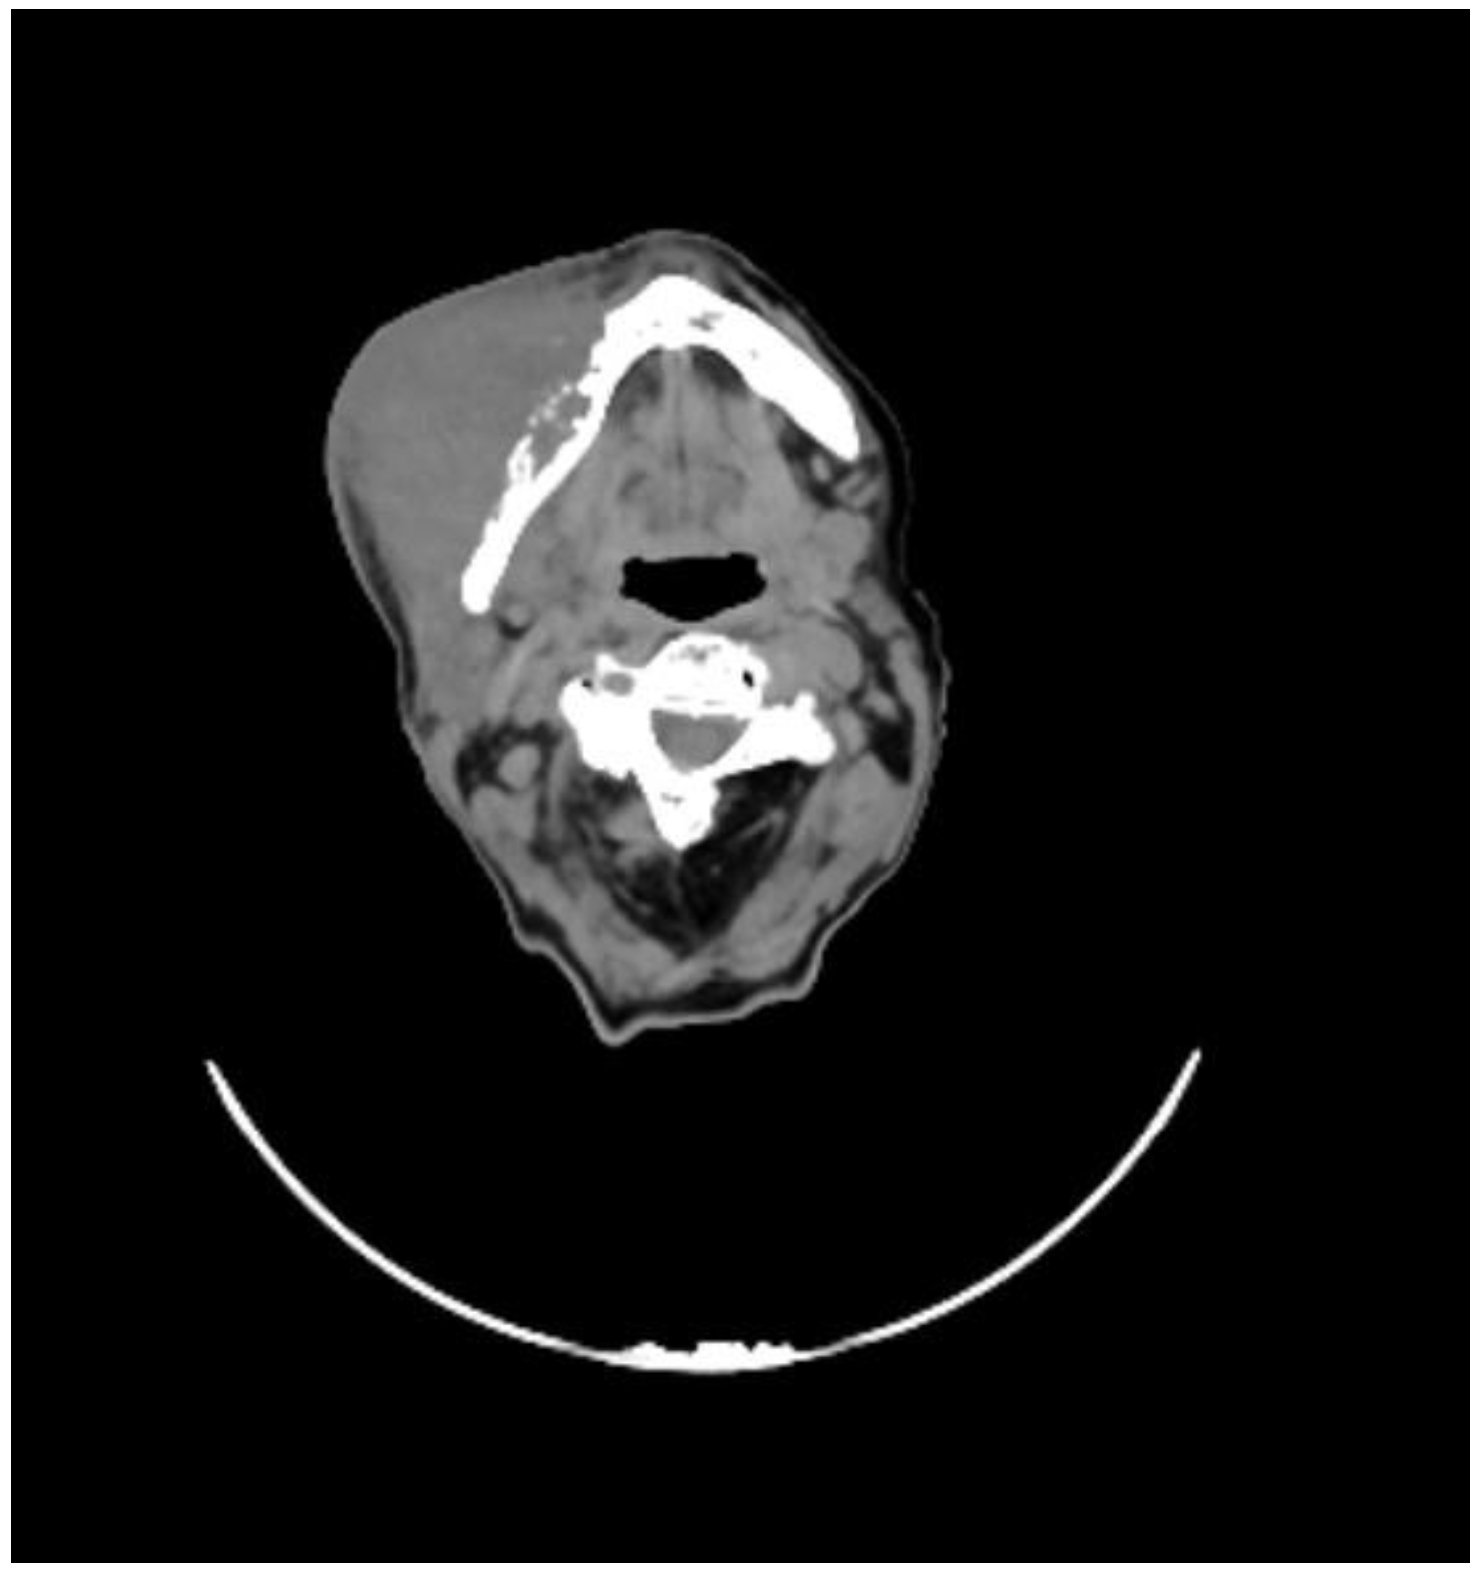

2. Case Presentation